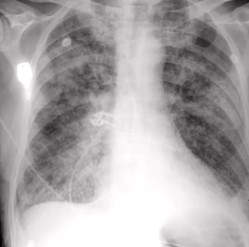

Radiografia de tórax: nota-se importante congestão pulmonar